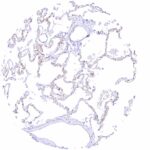

| Lung | Distinct PODXL staining of alveolar capillaries. | |

| Endothelium | Distinct PODXL staining of endothelial cells of predominantly small vessels in all tissues. | |

| Remarks | PODXL staining of endothelial cells of predominantly small vessels is seen in all tissues. |